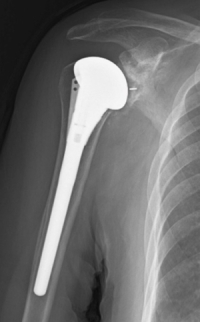

腱板の残存した変形性肩関節症に対しては解剖型人工肩関節置換術(TSA)を行っています。当院は人工関節センターが開設されており、安全に人工肩関節手術を行うことが可能です。

a. 解剖型人工関節 b.反転型人工関節